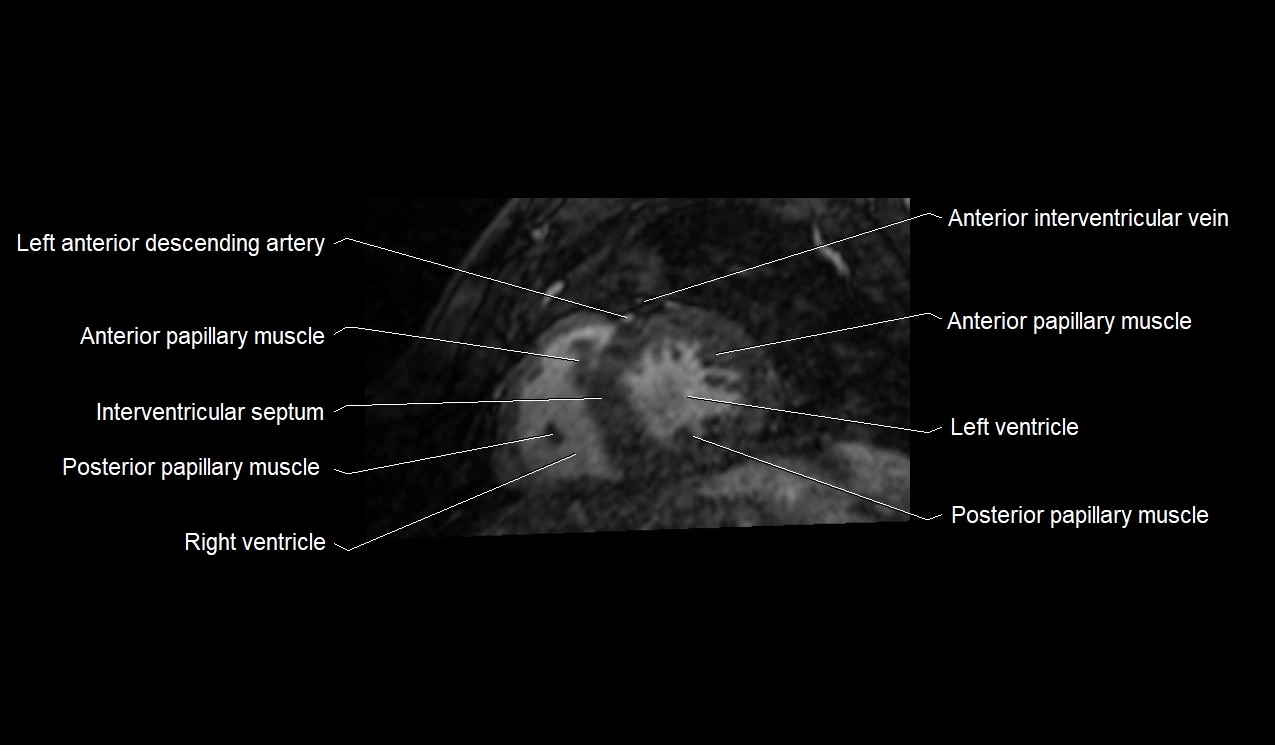

MRI image